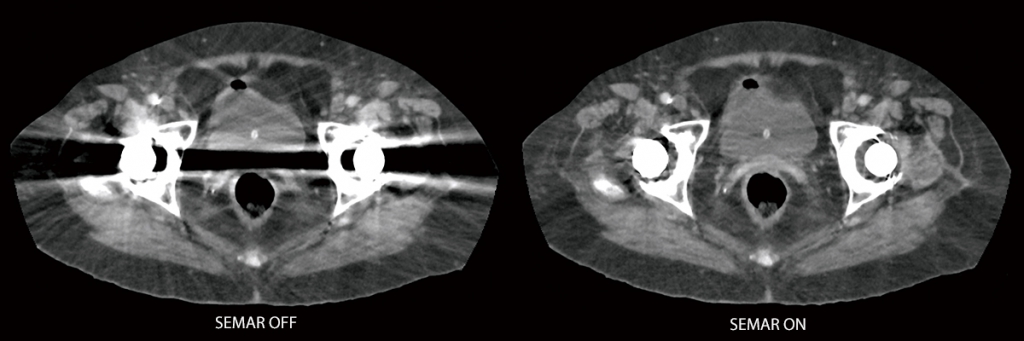

SEMAR (одноэтапное уменьшение артефактов металла)

Улучшенная визуализация кости и мягких тканей благодаря единому энергетическому сырью, основанному на снижении артефактов металла.